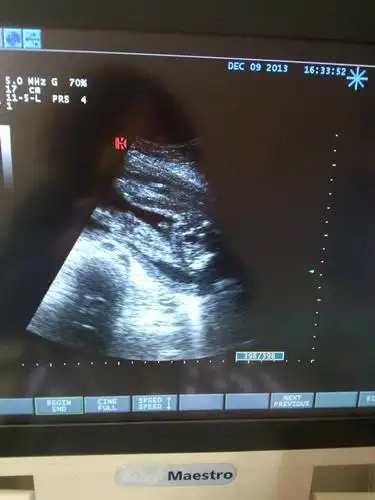

求大师,帮忙看看,男宝女宝?六个月图